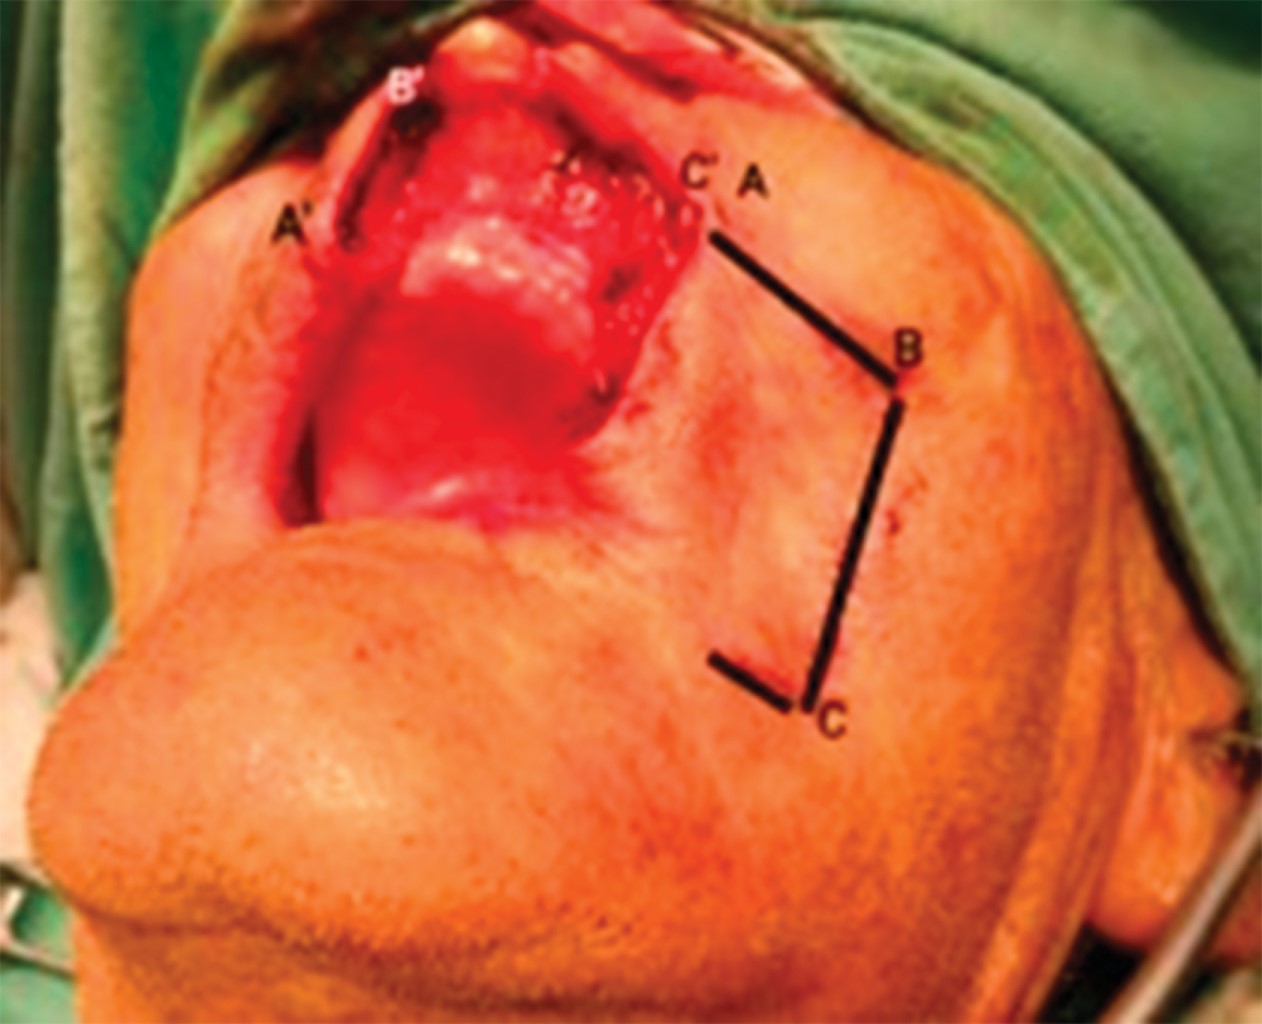

Basal cell carcinoma constitutes 80-90% of all skin cancers and is the most common tumor in humans. It causes a significant impact on the quality of life, with functional and aesthetic morbidity. The anatomical location of the tumor makes us consider reconstructive management, the lips being one of the most complex tumor sites to treat. The reconstruction of large defects of the upper lip constitutes a challenge for the surgeon due to the expectation its results generate not only functional, but also aesthetic. We present the case of a patient with an ulcerated nodular basal cell carcinoma on the upper lip, which was treated by excision and reconstruction with an ipsilateral Gillies fan flap and a contralateral perialar flap with good results.

Figure 1